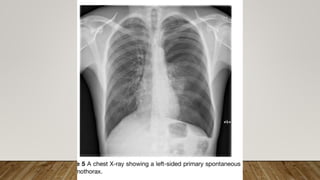

This document discusses pleural diseases. It was written by Eman Abdallah Aboelenein, who has an MSc and works as an assistant lecturer of hemato-oncology and bone marrow transplantation at the hematology unit of the internal medicine department of the faculty of medicine at Tanta University Hospitals. The author thanks the reader for their time and attention.